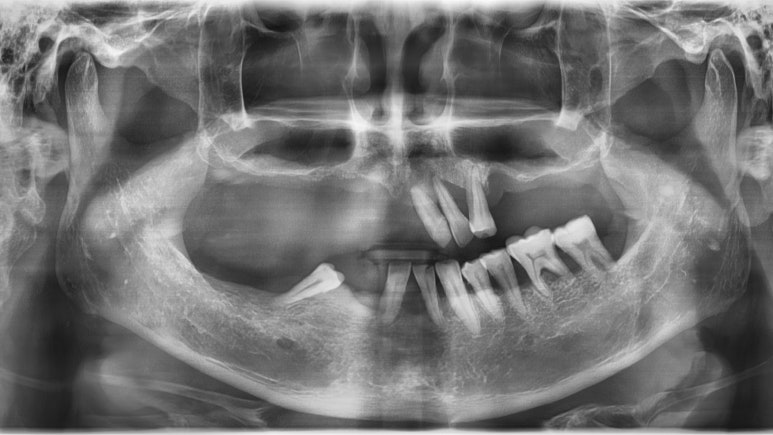

(아래 쪽은 원래 계획대로 진행되어 임플란트5개를 식립하였으며, 위 쪽은 환자가 도중에 2개의 임플란트만 심고 싶어하여 2개의 임플란트 식립)

처음과 비교했을 때 엄청난 차이를 보이죠.

이러한 세세한 시뮬레이션, ct를 이용한 컴퓨터 분석을 통해

더 정확하고 안전하게 적절한 위치에 임플란트를 식립할 수 있었으며

절개가 없는 비절개 방식을 이용한 인플란트로

수술시간이 짧고 실밥을 풀 필요가 없으며, 환자분의 만족도도 높습니다.